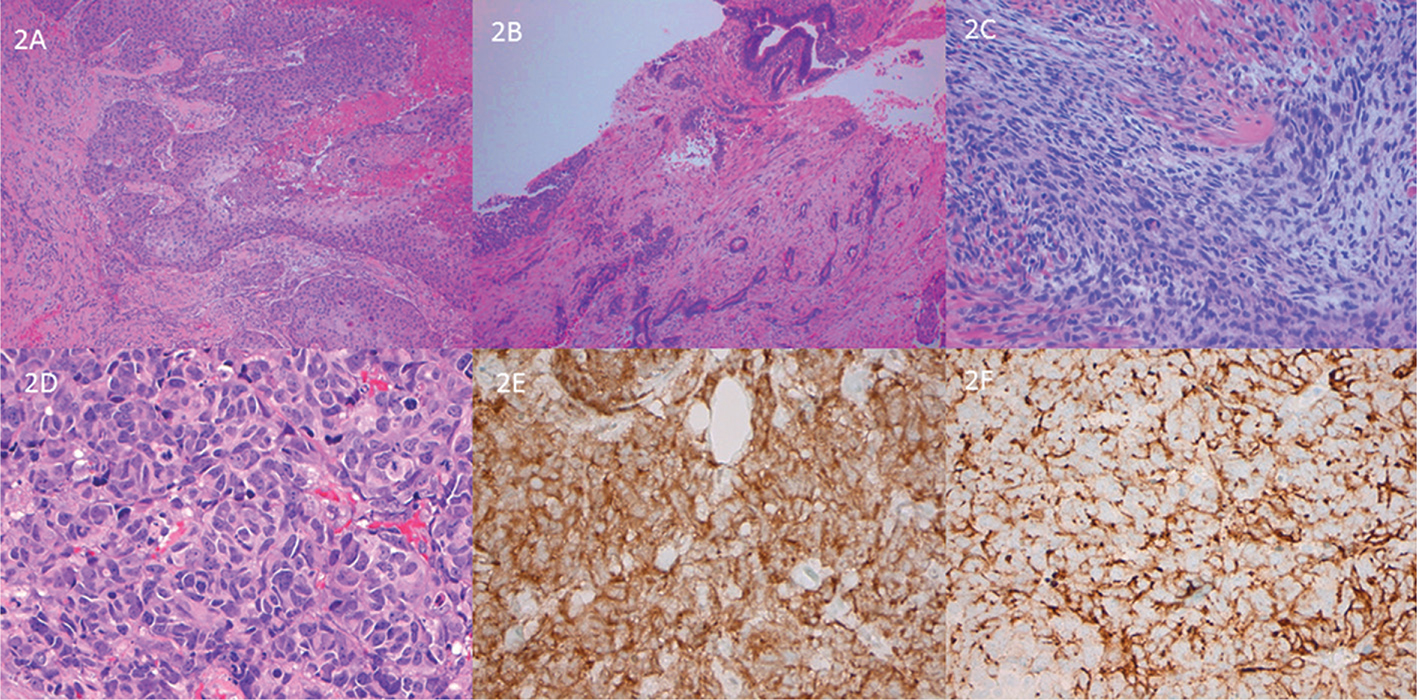

Fig 2

Figure 2. Divergent differentiation. Squamous differentiation (2A) and glandular differentiation (2B). Panel 2C highlights sarcomatoid features. Small cell carcinoma with nuclear moulding, hyperchromasia, mitoses (panel 2D). 2E synaptophysin and 2F chromogranin staining.

UROTHELIAL CARCINOMA WITH SQUAMOUS DIFFERENTIATION

Squamous differentiation is the most frequent line of divergent histology seen in high grade urothelial carcinoma (Figure 2A) and may be present in ~30% of such cases (36). The presence of keratinization and intercellular bridges define squamous histology. The presence of any urothelial carcinoma component (including carcinoma in situ) should be recorded and cases reported as urothelial carcinoma with squamous differentiation as it is thought that pure squamous cell carcinomas show less response to conventional chemotherapy (37, 38). The approximate percentage of the squamous component should be noted in the report. Squamous differentiation may be seen in the context of chronic irritation such as with stones, Schistosoma infection and neurogenic bladder with in-dwelling catheters (39, 40). Human papilloma virus (HPV) is not thought to be a causative agent of this divergent morphology. Some studies have reported worse outcome when squamous histology is present, which may be related to advanced stage at presentation. Both usual urothelial immunomarkers and squamous markers (desmoglein 3 and CK14) can be expressed (41).

UROTHELIAL CARCINOMA WITH GLANDULAR DIFFERENTIATION

A glandular component of urothelial carcinoma is less frequent than a squamous one and frequently recapitulates the appearance of enteric histology, resembling a colonic-type adenocarcinoma (Figure 2B). Another variation of glandular differentiation is the presence of mucinous type carcinoma with mucin pools containing either glands or signet ring cells. The presence of extracellular mucin differentiates signet ring cell glandular differentiation from a plasmacytoid urothelial carcinoma. An in-situ carcinoma with glandular phenotype may be seen in conjunction with invasive glandular differentiation (42). A pseudo-glandular appearance may be seen in conventional urothelial carcinoma whereby cell “drop-out” imparts a gland-like appearance. The presence of glandular morphology results in the acquisition of an alternate immuno-phenotype with expression of CK20 and CDX-2, typical of enteric lesions with either co-expression or loss of urothelial markers. The approximate percentage of glandular component should be noted in the report and in the absence of any urothelial carcinoma, the case should be considered as a pure adenocarcinoma. The presence of TERT promoter mutations may be helpful in this context as they are lacking in pure adenocarcinomas but will be present in ~70% of invasive urothelial carcinomas (43).

UROTHELIAL CARCINOMA WITH SARCOMATOID DIFFERENTIATION

Sarcomatoid differentiation comprises morphologic features of sarcoma and either histologic or immunohistochemical evidence of an epithelial component (Figure 2C). The sarcomatous areas are frequently undifferentiated, high grade spindle cells or show pleomorphic cells. Heterologous components (osteosarcoma, chondrosarcoma, angiosarcoma etc) may be identified and should be noted in the report. Cytokeratin stains may be required to identify the urothelial/epithelial areas but may also be positive in the sarcomatoid foci, as can p63 and GATA-3 (46). Metastatic disease is frequently present at diagnosis and the 5-year survival is poor (46, 47).

UROTHELIAL CARCINOMA WITH NEUROENDOCRINE DIFFERENTIATION

Small cell neuroendocrine carcinoma (Figure 2D) is much more frequent than large cell neuroendocrine carcinoma and often co-exists with conventional high grade urothelial carcinoma or other divergent morphology. Histologically, it resembles small cell carcinoma of the lung and exhibits staining for neuroendocrine markers (synaptophysin, chromogranin, CD56 etc- Figure E and F). Any amount of small cell morphology needs to be documented as it impacts chemotherapy selection and management. High rates of TP53 and RB1 mutations are noted and in keeping with its origin from urothelial carcinoma, TERT promoter mutations are frequent (48). Patients with small cell differentiation have poor prognosis including overall and disease specific survival (10).